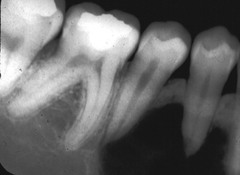

internal resorption

-round to ovoid radiolucency in the central part of the tooth -chronic inflammation -may see pinkish hue to crown if it is involved